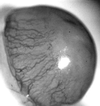

Onchocerciasis is a major cause of blindness. Although the World Health Organization has been successful in reducing onchocerciasis as a public health problem in parts of West Africa, there remain an estimated 17 million people infected with Onchocerca volvulus, the parasite that causes this disease. Ocular pathology can be manifested in any part of the eye, although disease manifestations are frequently characterized as either posterior or anterior eye disease. This review focuses on onchocerca-mediated keratitis that results from an inflammatory response in the anterior portion of the eye and summarizes what is currently known about human disease. This review also describes studies with experimental models that have been established to determine the immunological mechanisms underlying interstitial keratitis. The pathogenesis of keratitis is thought to be due to the host inflammatory response to degenerating parasites in the eye; therefore, the primary clinical symptoms of onchocercal keratitis (corneal opacification and neovascularization) are induced after injection of soluble O. volvulus antigens into the corneal stroma. Experimental approaches have demonstrated an essential role for sensitized T helper cells and shown that cytokines can regulate the severity of keratitis by controlling recruitment of inflammatory cells into the cornea. Chemokines are also important in inflammatory cell recruitment to the cornea, and their role in onchocerciasis is being examined. Further understanding of the molecular basis of the development of onchocercal keratitis may lead to novel approaches to immunologically based intervention.